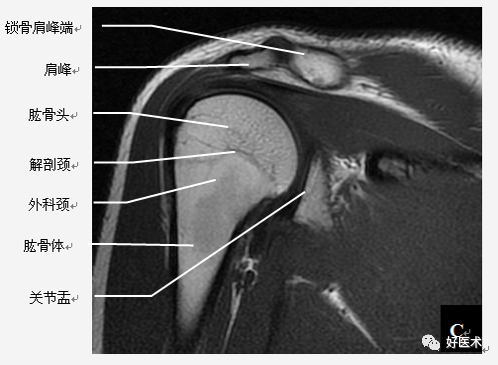

撞击综合征

当肩关节处于外展体位时,尤处于60°~120°时肩峰下空间缩小且肩腱袖刚好从中穿过,此时由于一些解剖结构病变引起冈上肌出口(肱骨头上方和肩峰下方间的间隙) 狭窄,即压迫肩峰下滑囊和/ 或冈上肌腱,引起以有肩部和上臂疼痛为特征的临床征候群。

肩袖、肱二头肌长头腱、肩峰下滑囊、喙肩弓、肩峰和肱骨头在综合征中起重要作用。

(1)肩峰下撞击综合征

1)病因:肩峰或喙肩弓结构异常、退行性变、创伤。

肩峰的形状:

-

Ⅰ型:扁平型;

Ⅱ型:弓型;

Ⅲ型:钩型